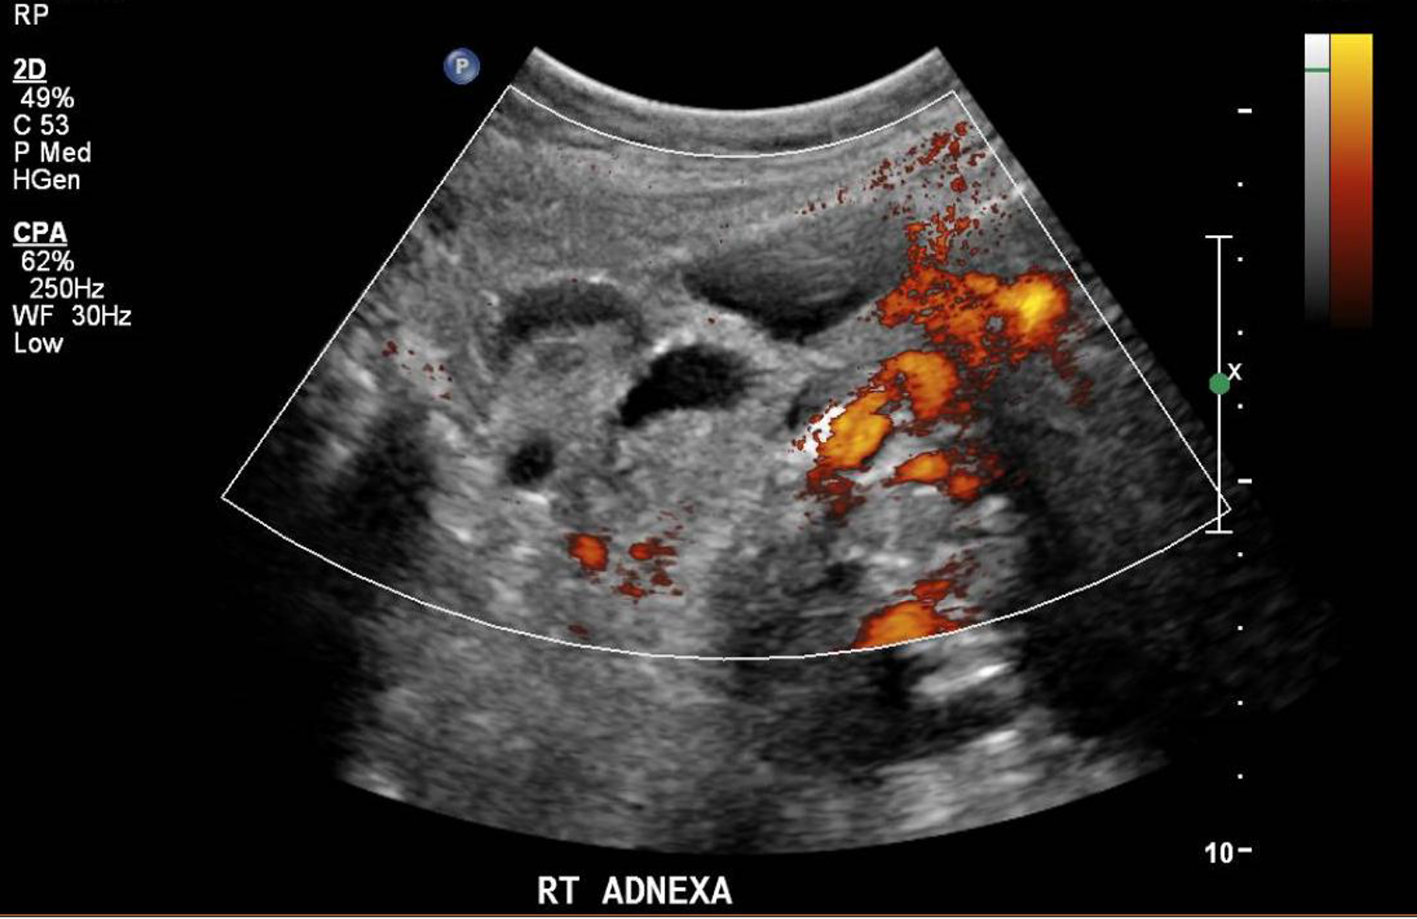

The ultrasound pelvis revealed a tubular cystic structure noted in the right adnexa adjacent to the right ovary measuring 4.6 × 3.4 × 4.3 cm. No definite whirlpool sign (twisted vascular pedicle corresponding to the broad ligament, fallopian tube, and adnexal and ovarian branches of the uterine artery or vein) was seen and the right ovary did not show typical signs of torsion (Figs. 1 and 2). Targeted ultrasound of the appendix was performed which was reported to be normal. She was empirically started on intravenous antibiotics and analgesics for her symptoms. However, on account of the persistence of her symptoms, a computed tomographic (CT) imaging for the abdomen and pelvis was performed on day 2 postpartum. The CT examination did not show any evidence of acute appendicitis and was suggestive of the right fallopian tube torsion (Fig. 3).

![]() Click for large image | Figure 1. Tubular structure adjacent to right adnexa on ultrasound pelvis. |

![]() Click for large image | Figure 2. Right adnexa on transvaginal ultrasound. |

The diagnostic contribution of ultrasound with Doppler remains controversial in the diagnosis of adnexal torsion [10]. The presence of blood flow on Doppler ultrasonography of the adnexa has a poor negative predictive value. In a study by Pena et al, 60% of the surgically confirmed cases of torsion had a normal Doppler flow, hence suggesting that normal blood flow cannot exclude a torsion [11]. The ultrasound features in IFTT usually constitute a normal-appearing uterus and ovaries with normal flow, physiological free fluid, a dilated tube with thickened, echogenic walls, or a convoluted echogenic mass thought to represent a thickened and torted fallopian tube [12].